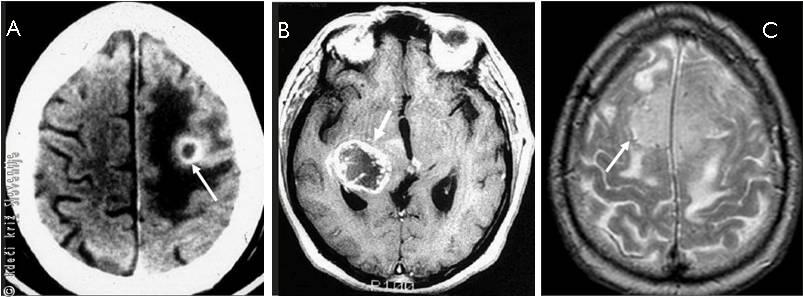

S – space-occupying lesions (angleško): Okvare, ki povzročajo pritisk na možgane zaradi novonastale spremembe v lobanji (npr. tumor). Povzročijo lahko postopno zoženje zavesti zaradi rasti novotvorbe in pritiska na možganske strukture (Slika 5).

Slika 5

A – Globinsko slikanje možganske metastaze raka pljuč.

B – Magnetno-resonančno slikanje rakastega (malignega) možganskega tumorja.

C – Magnetno-resonančno slikanje benignega (nerakastega) možganskega tumorja (meningeom – tumor možganskih ovojnic).

Prikazana stanja lahko privedejo do izgube zavesti zaradi pritiska ali pa zaradi povzročitve božjastnega napada.